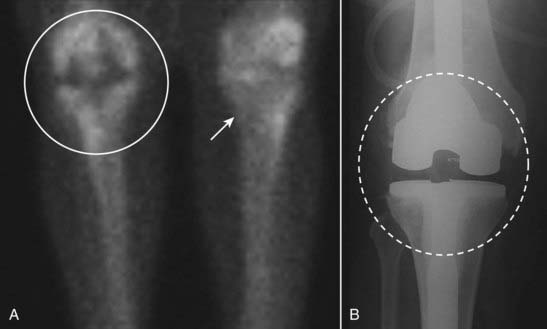

Photopenic lesions (photon-deficient lesions, cold spots) are areas of abnormally diminished or absent radiotracer uptake on the bone scan. These might be caused by an interruption of the blood supply so that no radiopharmaceutical can reach the area (e.g., avascular necrosis) or when a process is so destructive, no bone-forming elements remain (e.g., renal or thyroid metastases) (Fig. 4).

image

Figure 4 Photopenic abnormality.

Photopenic lesions (photon-deficient lesions, cold spots) are areas of abnormally diminished or absent radiotracer uptake on the bone scan. They can be produced by lesions such as avascular necrosis or when a process is so destructive, no bone-forming elements remain (e.g., renal or thyroid metastases). They can also be produced by a prosthesis, which can obviously not extract the radiotracer as normal bone does. In this case, a photopenic area is seen in the right knee (white circle) compared to left knee (white arrow) (A), produced by a metallic knee replacement seen better on the conventional radiograph (dashed circle in B).